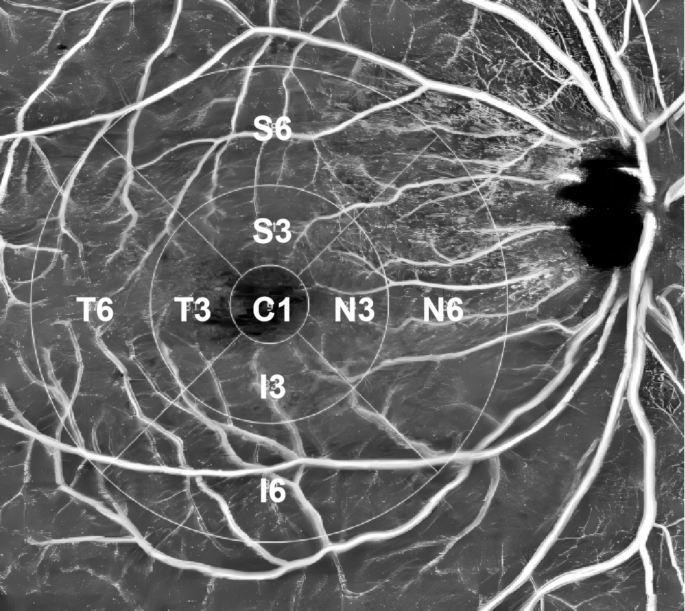

Macular topography followed the Early Treatment Diabetic Retinopathy Study (ETDRS) grid centered on the fovea, comprising three concentric areas: the central 1-mm circle (foveal region), an annulus from 1 to 3 mm (parafoveal region), and an annulus from 3 to 6 mm (perifoveal region). The parafoveal and perifoveal rings were further subdivided into four quadrants—superior (S), inferior (I), nasal (N), and temporal (T) (Fig. 2)19. Based on this grid, both structural and vascular images were partitioned into nine subfields (Figs. 2 and 3). The final analysis included the following parameters: SVD, GCC thickness, CT, CVI, and CCD.

Illustration of the macular ETDRS grid for retinal and choroidal analysis. The macular region was divided into three concentric rings with diameters of 1 mm, 3 mm, and 6 mm centered on the fovea. Sectors are defined as follows: C1, central fovea (0–1 mm); S3, superior sector within 1–3 mm; S6, superior sector within 3–6 mm; I3, inferior sector within 1–3 mm; I6, inferior sector within 3–6 mm; N3, nasal sector within 1–3 mm; N6, nasal sector within 3–6 mm; T3, temporal sector within 1–3 mm; and T6, temporal sector within 3–6 mm.